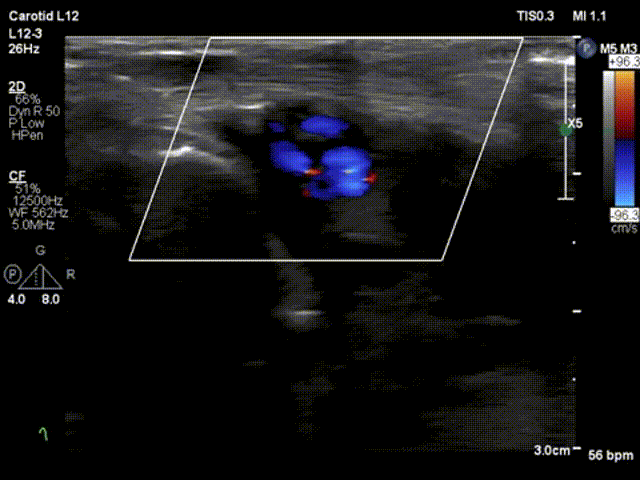

图1.dTRA形成动静脉瘘的照片、超声表现和血管造影图像。

(A)观察到扩张的头静脉。(B)箭头显示动静脉瘘的入口,即桡动脉与静脉连接处。浅表超声检查发现远端桡动脉有一个直径为2.0mm、流速为3.75m/s的动静脉瘘。(C)桡动脉造影。显示远端桡动脉与手背静脉网之间存在分流,并且头静脉和贵要静脉显影。分流位于桡动脉至靠近拇指掌骨的静脉处。(D)常见的远端桡动脉穿刺部位(三角形)和本例的穿刺部位(星形)。

超声检查在穿刺部位发现了一个动静脉瘘(AVF)。分流处的最大流速为3.75m/s,瘘口直径为2.0mm(图1B,视频1)。

箭头显示动静脉瘘的入口,即桡动脉与静脉连接处。